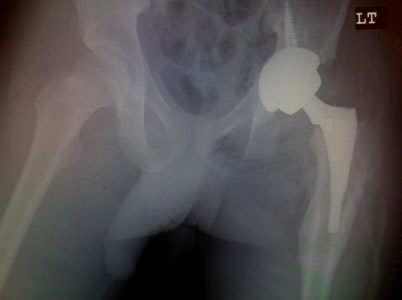

He was in his usual state of good health until age 14 when he became spontaneously septic. He was placed on ID pressors and subsequently lost his toes from vasoconstriction. He developed AVN of the femoral head. He does not think he was on any prednisone. He was then treated with a hip fusion. During the hip fusion the surgeon decided to do a subtrochanteric osteotomy which left the patient with a deformed proximal femur. He was placed in a hip spica cast for over 5 months. He believes he was also infected in the cast, but after speaking to him it sounds as if he had wound breakdown from the cast and not a deep infection.

|

| |

Modified Anterior-lateral Watson-Jones surgical approach. |

| You will notice when you take out the pelvic obliquity it is 45 degrees |